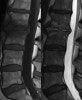

MRI : 추간강 감염(Disc space infection)

MRI : 추간판염(Discitis)

MRI : 경막외 농양(Epidural space abscess)